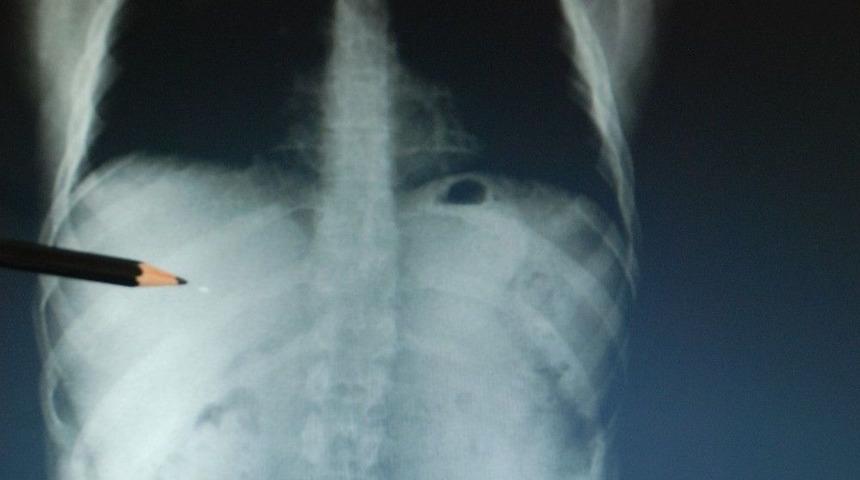

Ankara’da 15 Temmuz’da hain darbe kalkışmasında helikopterden açılan ateş sonucu yaralanan Mecnun Ekinci, göğsündeki şarapnel parçası ile yaşıyor.Ankara’da yaşayan evli ve iki çocuk babası Mecnun Ekinci, rahatsızlanarak Tokat Devlet Hastanesine kaldırılan babasını görmek için memleketi Tokat’a geldi. 15 Temmuz hain darbe girişiminde yaşadıklarını dile getiren Ekinci, sağ göğsünün altından giren şarapnel parçası ile yaşadığını söyledi. Cumhurbaşkanı Recep Tayyip Erdoğan’ın halka çağrıda bulunması ile birlikte ailesi ile vedalaşarak sokağa çıktığını ifade eden Ekinci, "Dış kapı köprüsüne kadar yürüyerek gittim. Gençlik parkının oraya gittiğimde uçaklar alçak uçuş yapıyordu. Tankın araçları ezerek geldiğini gördük. O hainleri tankın içinden çıkartmak istedik başarılı olamadık. Sonra "Genelkurmayın önünde askerimizi polisimizin ölüyor, oluk oluk kan akıyor" denilmesi üzerine tankın üzerine çıkarak Allah’ını peygamberini seven Genelkurmay’ın önüne gelsin diye bağırarak arkadaşlara öncülük yaparak Cumhuriyet Meydanına intikal ettik. Oraya gittiğimizde helikopter sivil vatandaşları tarıyordu. Biz öncelikle yaralılara yardım etmek ve Genel Kurmayı savunmak için gittik. Bizi tekrar taradılar, o esnada ben helikopterin atmış olduğu ateşle yaralandım. Beni oradan hastaneye götürdüler" dedi.Vücudunda şarapnel parçası ile yaşadığını ifade eden Ekinci, "Bazen şarapnel parçası nedeni ile acı hissediyorum. Doktorlar enfeksiyon olursa alırız dediler. Benim tek dileğim şu idi, Bakanımıza da devlet övünç madalyası takdim ederken söyledim. Zeytindalı Harekatına katılmak istediğimi söyledim. Ankara Valimiz asker sayımızın yeterli olduğunu herhangi birşey olduğunda size bilgi vereceğiz dediler. Ben sadece şehit olmadığıma üzülüyorum" diye konuştu.